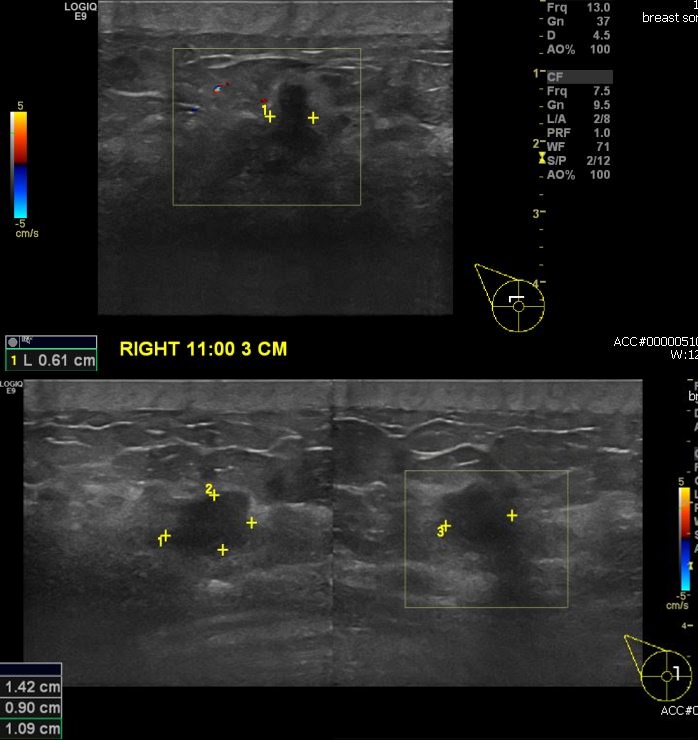

우측 유방에 만져지는 멍울로 내원하신 40대 여성분으로 초음파상 우측 11시 방향에

3mc 떨어진 거리의 만져지는 멍울 조직검사 시행하여 우측 침윤성 유방암 진단되었습니다.